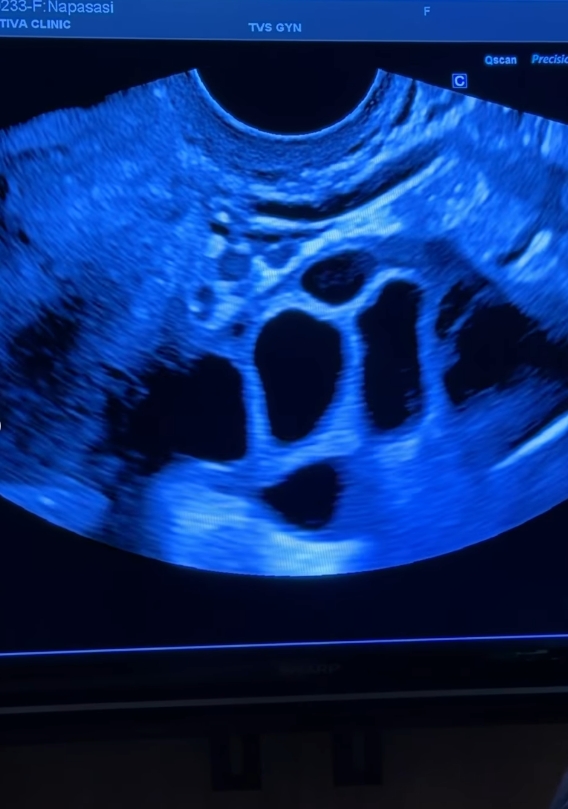

กระบวนการฝากไข่ของหมวยเสร็จเรียบร้อยแล้วค่ะ ก่อนอายุครบ 35 ปีบริบูรณ์ ได้ไข่ทั้งหมด 19 ใบนะคะ เย่!

เกือบครบ 3 อาทิตย์แล้วตั้งแต่วันแรกที่เริ่มฉีดยากระตุ้นไข่ บอกเลยค่ะช่วงแรกตื่นเต้นทุกวัน กลัวว่าฮอร์โมนและอารมณ์จะไม่ปกติ จะไม่มีแรงทำงาน ตั้งใจดูแลตัวเองแบบละเอียดที่สุดเท่าที่เคยทำมา ทำตามคำแนะนำของคุณหมอ(อาจารย์อัญ)ทุกอย่าง และผลที่ได้คือฮอร์โมนไม่สวิงเลย ยังมีเอนเนอร์จี้เหมือนเดิม ตัวบวมน้อยมาก(มีแค่ช่วงท้องล่างที่บวม ตึงขึ้น) แฮปปี้มาก รู้สึกว่าการฝากไข่ชิวไปเลยค่ะ

สำหรับมายด์การตัดสินใจครั้งนี้คือการให้ทางเลือกกับอนาคตของตัวเอง อยากวางแผนในวันที่ร่างกายยังแข็งแรง บอกเลยค่ะว่าเลือกไม่ผิดจริงๆที่มาที่นี่ คุณหมออัญใส่ใจให้รายละเอียดชัดเจนดีมาก พี่ๆน่ารักทุกคน แนะนำเลยนะคะใครกำลังอยากหาที่ฝากไข่ ลองมาปรึกษาที่นี่ได้เลยค่ะ:)